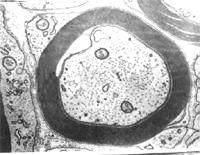

有髓神經纖維有髓神經纖維(myelinated nerve fiber)由軸突(或樹突)、髓鞘、神經膜構成。髓鞘(myelin sheath)及神經膜(neurolemma)呈鞘狀包裹在軸突的周圍。在軸突的起始部無髓鞘包裹,稱此部為起始段(initial segment)起始段遠側的軸突部分,髓鞘呈節段包捲軸突,形似藕節,其間斷部位,軸膜裸露,,可發生膜電位變化,稱此部位為神經纖維節(node of nerve fiber),又稱郎飛結(Ranvier node)。兩個相鄰結之間的一段,稱結間體(internode),長約0.5~lmm,它是由一個施萬細胞所形成的髓鞘及其周圍的神經膜構成。施萬細胞核呈長橢圓形,位於髓鞘邊緣的少量胞質內。髓鞘主要是由類脂質和蛋白質所組成,稱為髓磷脂(myelin)在常規染色標本上,因髓鞘中的類脂被溶解,僅見殘存的蛋白質呈網狀,稱神經角演網(neurokeratin network)。在鋨酸浸染標本上,髓鞘呈黑色,其中還可見數個呈漏斗形的斜裂,稱髓鞘切跡(incisure of myelin)或施-蘭切跡(Schmidt-Lanterman incisure)。電鏡下,髓鞘為明暗相間的同心圓板層排列。髓鞘有保護和絕緣作用,可防 止神經衝動的擴散。

髓鞘的形成:在有髓神經纖維發生中,伴隨軸突一起生長的施萬細胞表面凹陷成一縱溝,軸突位於縱溝內,溝緣的胞膜相貼形成軸突系膜(mesaxon)。軸突系膜不斷伸長並反覆包捲軸突,把胞質擠至細胞的內、外邊緣及兩端(即靠近郎氏結處),從而形成許多同心圓的螺鏇膜板層,即為髓鞘。故髓鞘乃成自施萬細胞的胞膜,屬施萬細胞的一部分。施萬細胞的胞質除見於細胞的外、內邊緣和兩端外,還見於髓鞘板層內的施-蘭切跡。該切跡構成螺鏇形的胞質通道,並與細胞外、內邊緣的胞質相通。